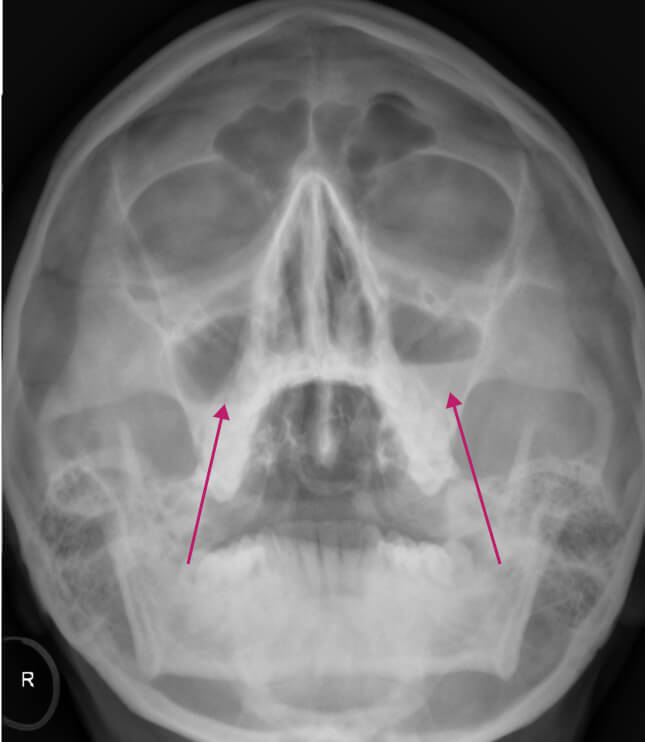

Хурц хэлбэрийн дайвар хөндийн үрэвсэл нь хамар, хамрын дайвар хөндийн үрэвслийн үед элбэг тохиолддог, ингэхдээ хамрын хөндийн дайвар салстын үрэвсэл явагддаг. Хурц хэлбэрийн хамар, хамрын дайвар хөндийн үрэвсэл үзлэг ба асуумжийн үед сайн оношлогддог. Нянгийн гаралтай халдвар эсвэл хүндрэл үүссэн сэжиг байвал рентген зураг авах аргаар оношилгоог хийдэг.

Рентгений баруун талын зургийг харахад дээд эрүүний хоёр талт хурц хэлбэрийн идээт хамрын дайвар хөндийн үрэвсэл байгааг харуулсан байна, үүгээр дайвар хөндийн хонход хэвтээ түвшинд шингэн хуримтлагдсан байгааг баталж болно. Зүүн хонх нь ойролцоогоор 1/3-ээр илүү шингэнтэй, баруун хонх нь тал хэсэг нь шингэнээр дүүрсэн байна.